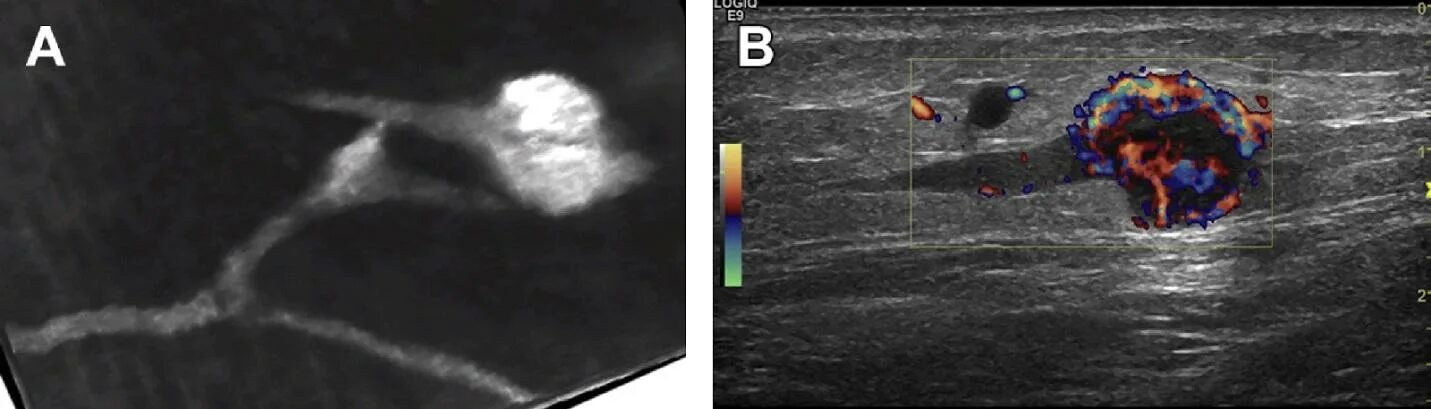

Лимфоузлы можно при раке